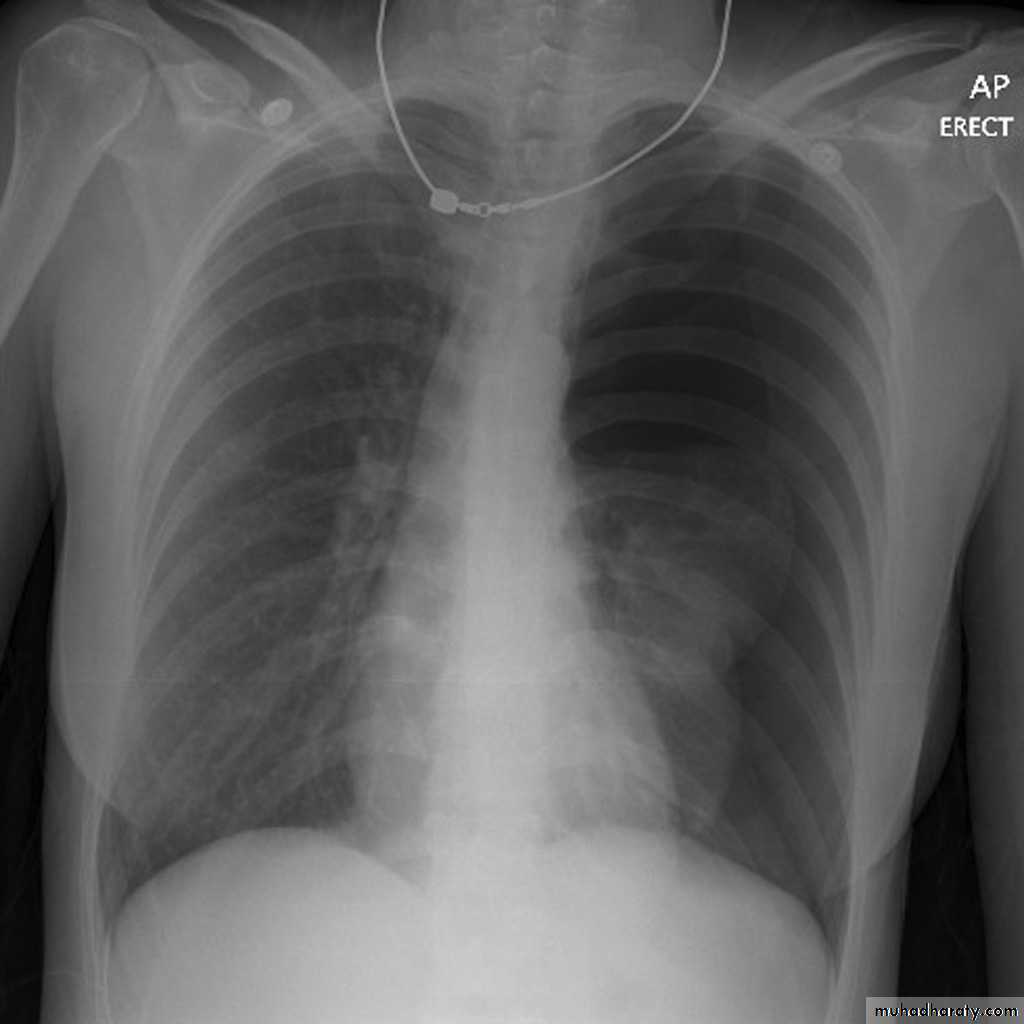

• Check up chest x-ray

History: dyspnea, weight loss, dehydration with poor immunity

History; too shy to take of his shirt in the pool!

What is the difference?

Differential diagnosis?